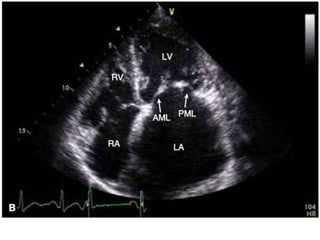

Views

1. PLAX

2. PSAX at MV level

3. A4CV

2 Dimensional (Initial Assessment)

• Restricted motion and diastolic motion of

leaflets ( hockey stick sign)

• Thickening and calcification of leaflets and

chordae

Views 1. PLAX 2. PSAXat MV level 3. A4CV

2 Dimensional (InitialAssessment) • Restricted motion and diastolic motion of leaflets ( hockey stick sign) • Thickening and calcification of leaflets and chordae